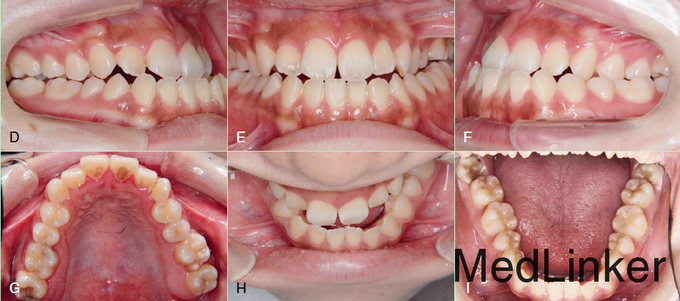

18y女性,要求解决地包天面型及咬合不佳等问题

面部不对称,III类,上颌发育不足,下颌发育过度,长面型,前牙开合,露龈笑。上前牙唇倾,下前牙舌倾代偿。尖牙磨牙近中关系